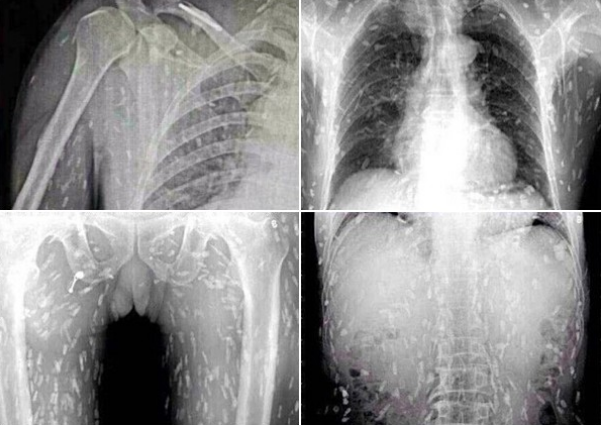

医師の話では、女性の体内の寄生虫の一部はすでに死に、石灰化しており、全身の痛み以外に眼球突出や

網膜出血といった症状も見られたとのこと。治療はすぐに行われたものの、一部の寄生虫は体外に排出されず、

女性には後遺症が現れる可能性も否めないという。